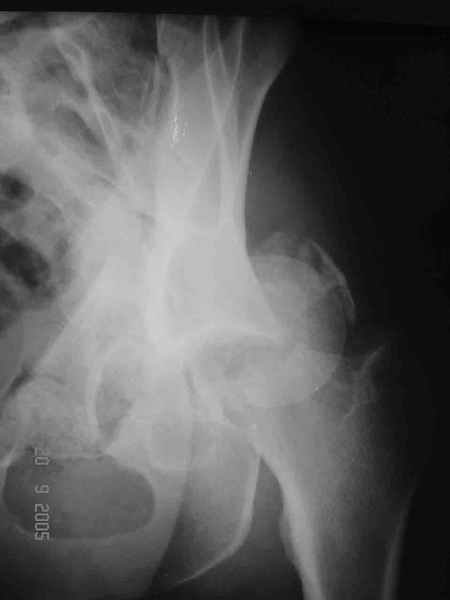

Re: Перелом acetabulum и проксимального отдела бед

Alexey Smirnov 26 Сентябрь 2005, 23:36

Привет! Вот недавно прооперировали похожий на ваш случай - впадина + шейка (правда у нас впадина поперечный+задний край). После травмы прошло 4 недели. мужчине 46 лет. С такой комбинацией все показания к первичному протезированию. Морально и технически мы к этому уже созрели.Но больной не собрал денег на протез. Выполнили остеосинтез впадины и шейки, прекрасно понимая, что головка вскоре рассосется, мы хотя бы надемся что к этому времени таз срастется, как говорится создали все условия для дальнейшего протезирования (может, и протез в последующем подешевле будет, в смысле, без укрепляющего кольца?). Привет Рункову!

Рунков 27 Сентябрь 2005, 09:57

Привет Алекей! Сделано неплохо, поздравляю, хотя второй винтик можно было бы и подлиннее в шейку загнать! Пара вопроов: доступ такой же? головка была свободной или висела на капсуле?

Отправитель: Алексей Смирнов 27 Сентябрь 2005, 22:35

Согласен, можно было и подлиннее. Доступ такой же - чрезвертельный, только разрез кожи прямой (а не Y, чего то я разницы не ощущаю). Головка была абсолютно свободной (то есть во время остеосинтеза таза лежала в стакане и не мешалась). Шансов, что она прирастет 0,00001%. Хотели даже выбросить, но привинтили как временный биологический протез (читай свободный трансплантат), чтоб на период срастания таза бедро проксимально не ушло (может ортопеды потом спасибо скажут). Ну а у вас первичное протезирование при переломе впадины тоже пока полько в планах?